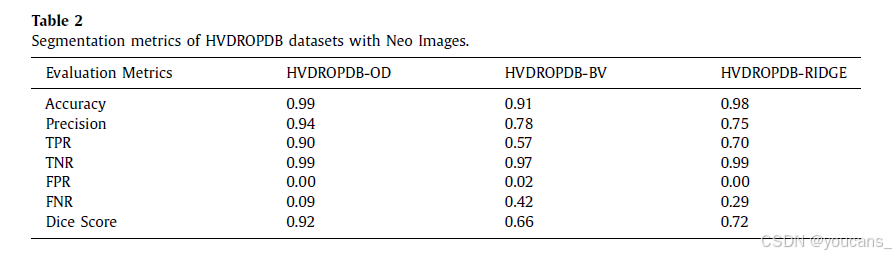

使用 AG U-Net 方法[7] 对 Neo 和 RetCam 图像进行分割。对 HVDROPDB 数据集进行分割的性能指标如表2 和表3 所示。

所有数据集都以 70:10:20 的比例划分为训练集、验证集和测试集,随机状态的种子数为42。